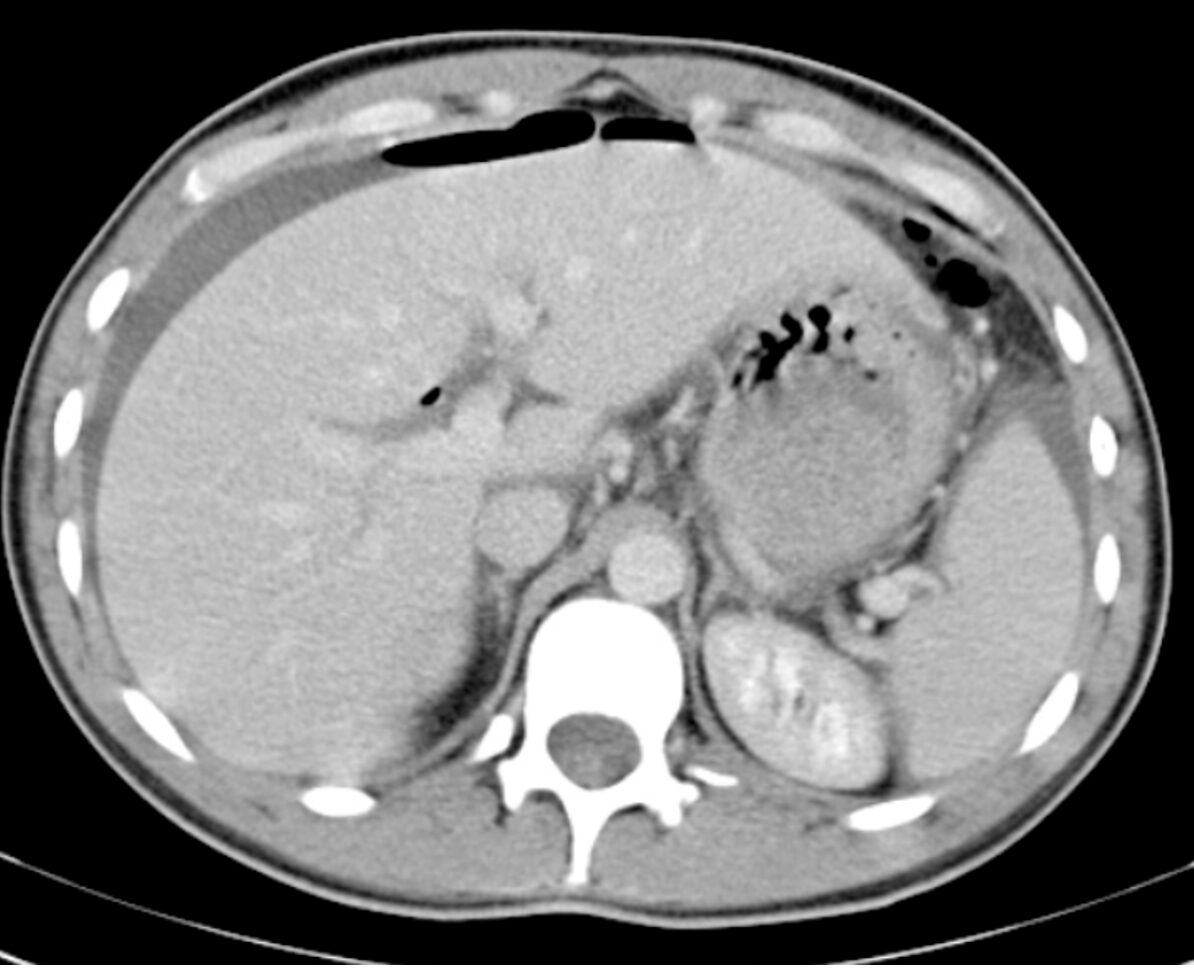

Computed Tomography (CT):

- Advantages:12,31

- Can detect even minimal free air with significant accuracy.

- Can indicate the location and size of the perforation.

- Can also diagnose other causes of acute abdomen.32

Figure 6. Pneumoperitoneum with free air extending into an umbilical hernia on axial CT abdomen/pelvis using lung window. This patient suffered a perforated viscus secondary to malignancy. Source: Di Muzio B, Pneumoperitoneum. Case study, Radiopaedia.org (Accessed on 09 Nov 2025) https://doi.org/10.53347/rID-19130

Figure 7. Pneumoperitoneum anterior to the liver on axial CT abdomen/pelvis. The cause of the free air was never identified for this patient. Source: Puyó Vera D, Pneumoperitoneum. Case study, Radiopaedia.org (Accessed on 09 Nov 2025) https://doi.org/10.53347/rID-23601